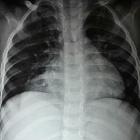

Unusual

association of parvo-virus with Morgagni hernia, mistaken for patch of consolidation. Chest X-ray PA view shows radio-opacity involving the RT cardio-phrenic angle partially silhouetting the RT cardiac border. The radio-opacity showed sharp interface with adjacent lung parenchyma.